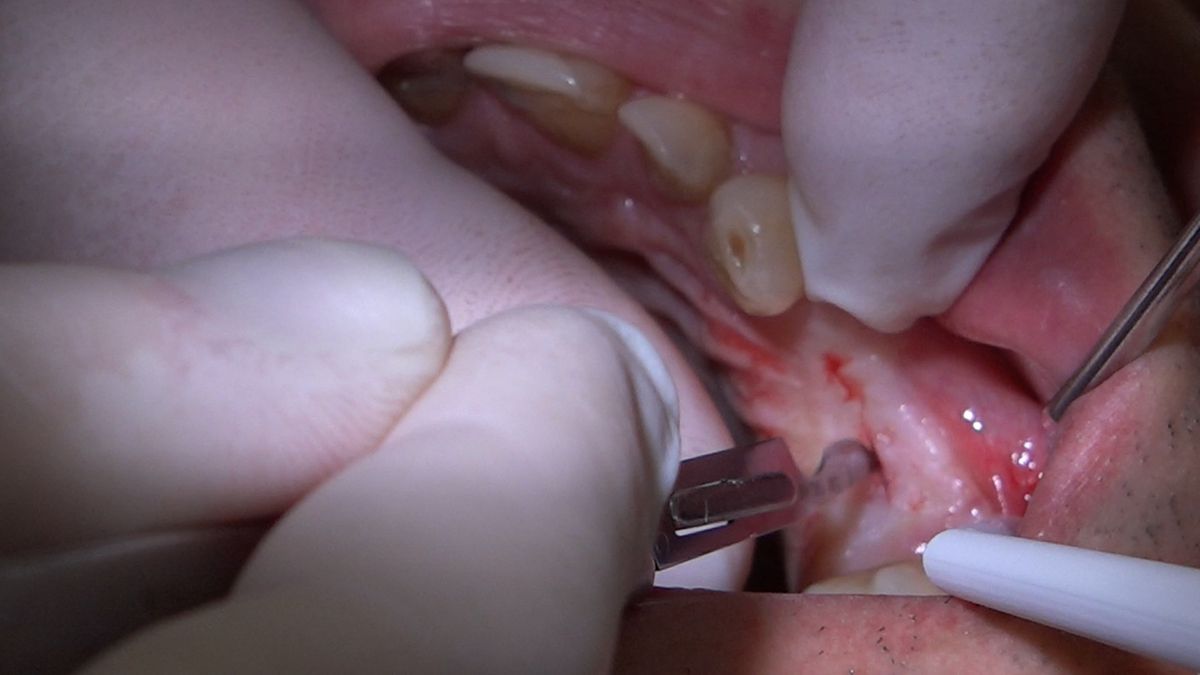

Tematem przewodnim 3 Sesji X Sezonu Practiculum Implantologii była protetyka na implantach. Lekarze przeprowadzili wiele procedur implantoprotetycznych pod kierunkiem dr n.med. Violetty Szycik, w tym oddanie prac przykręcanych i odsłonięcie implantów. Pod kierunkiem dr Małgorzaty Piotrowskiej wykonywali pobieranie wycisków z poziomu implantów tradycyjnie i za pomocą skanera. Zabiegi i ćwiczenia poprzedziły wykłady, które przeprowadził także technik dentystyczny Marek Wiligała.